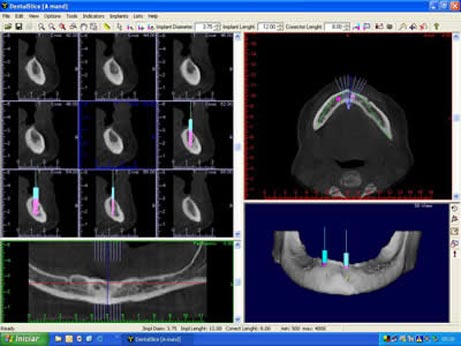

Para trabalhar no DentalSlice basta solicitar na Clinica Serraro a tomografia computadorizada, onde as imagens DICOM (arquivos da tomografia) serão convertidas para o ambiente DentalSlice criando um arquivo que será enviado para o cirurgião dentista.

O Dental Slice é uma ferramenta de planejamento implantodôntico pré-operatório, desenhado para oferecer auxílio cirúrgico-protético com alto nível de precisão e aumentar a margem de segurança no tratamento.

O programa foi projetado para rodar em computadores pessoais e ambiente Windows.

O programa é acessível a qualquer cirurgião dentista e permite que o planejamento seja realizado pela própria equipe que vai realizar a cirurgia. As imagens também podem ser segmentadas, oferecendo melhor visualização de detalhes, como por exemplo do seio maxilar, canal da mandíbula ou de lesões.